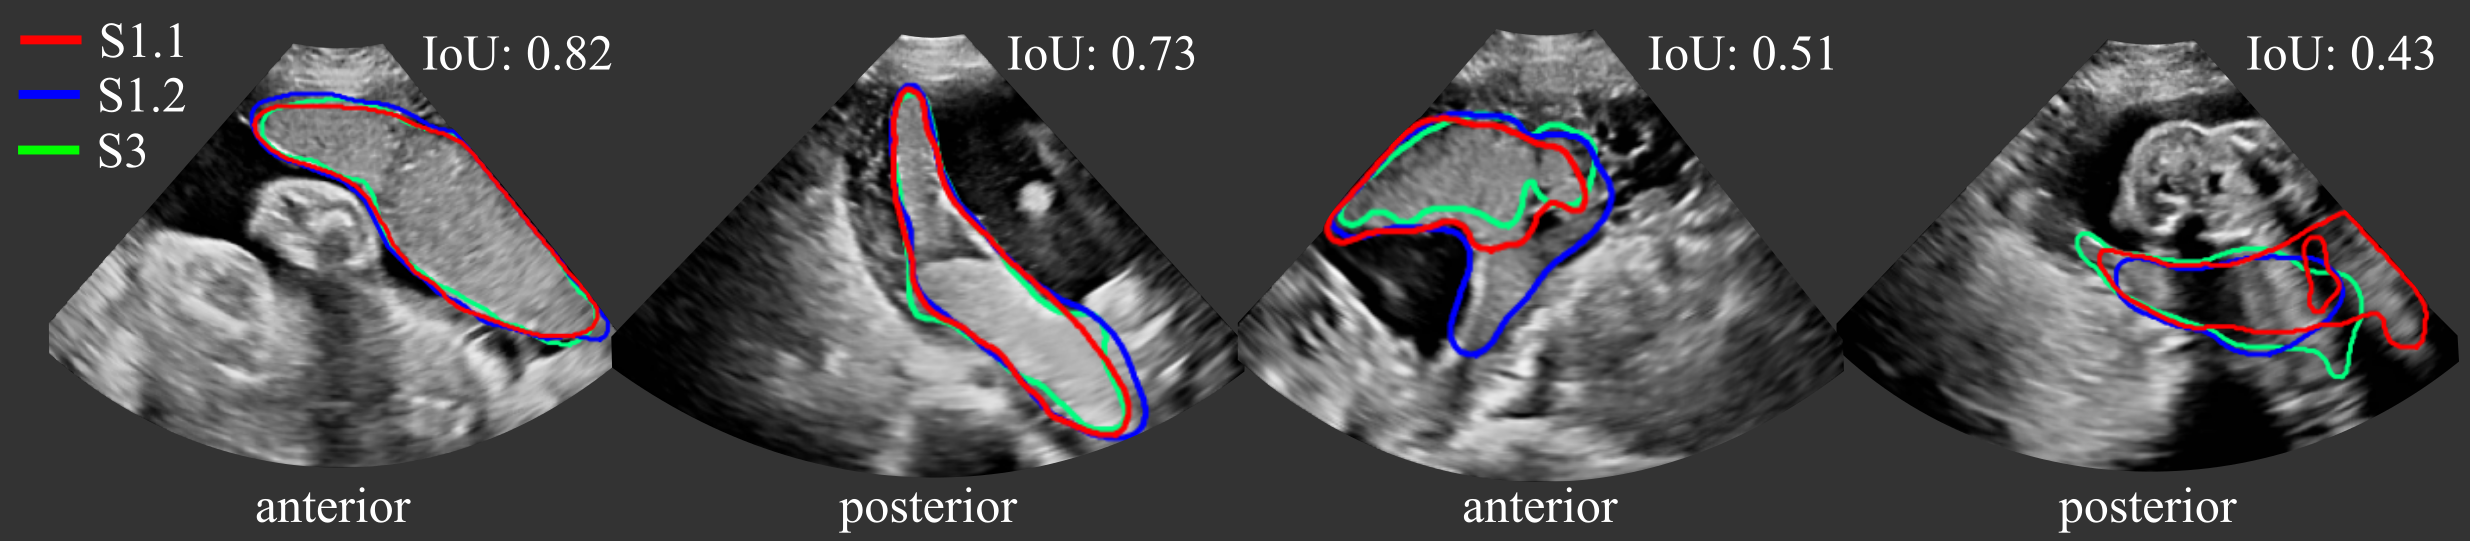

(ii) Variability and uncertainty. In a second set of experiments, we investigate the inter- and intra-rater variability of the manual segmentations and compare the variability and uncertainty in automatic segmentations. We measure the variability on a subset of the test data, for which three manual annotations are available, as described in Sec. 3.2. The intra-rater variability is the agreement between S1.1 and S1.2 and the inter-rater between S1.1 and S3. We compare the automatic segmentation to S1.1 (intra) and S3 (inter). The agreement between pairs of segmentations is measured using Dice, IoU, ASD and RHD.

We investigated the inter- and intra-observer variability for the manual annotation of placental tissue in 3D US. In each fold, we use a subset of the test set, for which three manual annotations are available, as described in Section 3.2. Figure 6 (a) shows the agreement of the segmentations as measured by Dice. We compared the agreement between manual raters S1.1 and S1.2 (intra-variability) and S1.1 and S3 (inter-rater variability), and Figure 7 shows examples with best and worst intra- and inter-observer agreement. In addition, we assess the agreement between manual and automatic segmentations (UNet and MTUNet), which are summerized under the term intra with reference S1.1 and inter with reference S3 in Fig. 6.

Comparing the agreement between manual annotations (plain white bars in Fig. 6), we observe that the intra-observer agreement is higher than the inter-observer agreement for all measures. The difference is statistically significant for anterior placentas with a moderate effect size and for posterior placentas with a strong effect size, denoted by one and two asterisks, respectively, above the bar for inter-rater agreement.

This suggests that the manual annotation of the placenta in US is a subjective task. In all cases and for all measures, the agreement in segmenting posterior placentas is smaller than in anterior placentas, emphasizing that the segmentation of posterior placentas is more ambiguous, possibly due to image artifacts. This is in line with the observation of the previous experiment, that the automatic segmentation models perform worse for posterior than for anterior placentas.

The intra-observer comparison of anterior placentas achieved the best agreement with a Dice of , an IoU of , an ASD of and a RHD of . These values can be therefore interpreted as an upper bound and the range between inter- and intra-observer agreement as the desired performance of any automatic segmentation model. For anterior placentas, both the baseline model UNet and our best performing model MTUNet, as selected in the previous experiment, lie within intra- and inter-rater variability with no significant difference () between the segmentation agreements. For posterior placentas, there is a statistically significant difference (with a moderate effect size) for the baseline model UNet, but not for MTUNet. The multi-task approach increases the performance and reduces the variance for all measures. The same trend is observed for IoU, ASD and RHD (see Fig. 13 in the appendix).